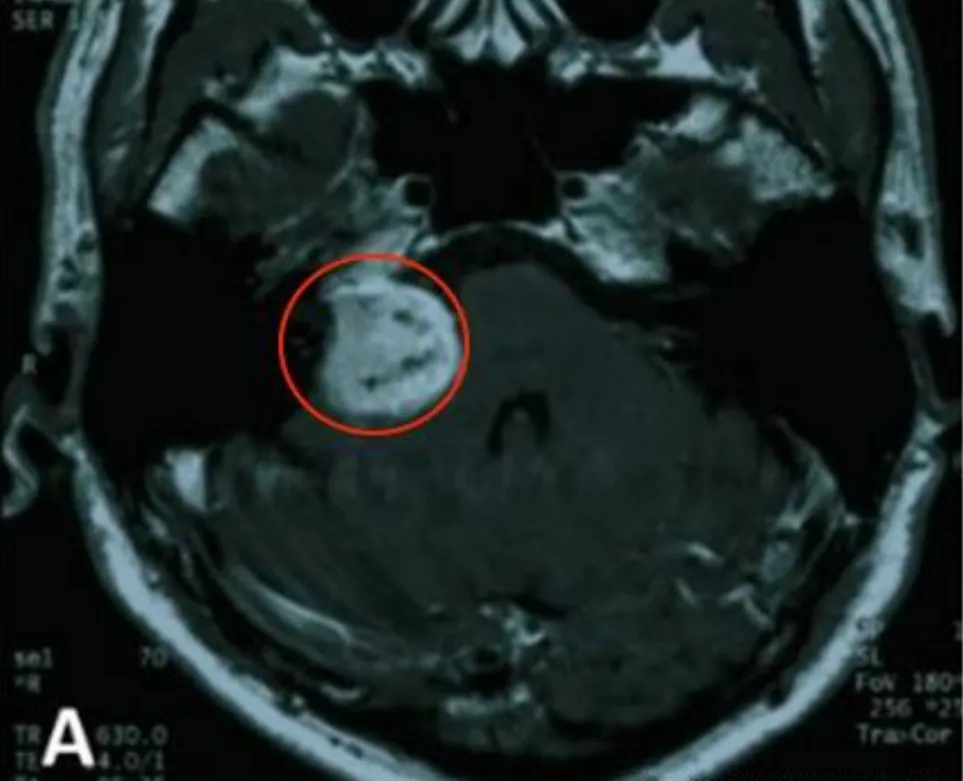

病例初始于体检意外发现听神经瘤,肿瘤位置接近脑干生命中枢...

齐奶奶的临床进程呈现听神经瘤典型发展规律。听神经瘤作为桥...

检查结果左侧听神经瘤诊断明确。术前评估显示患者已出现轻度...